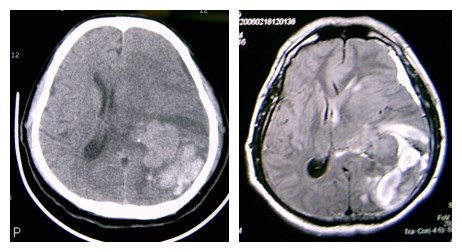

(1)注意识别脑瘤卒中的平扫CT及 MIR片特点:①多为形态不规则密度不均匀的混杂密度病灶,而高血压脑出血多为密度较均匀的类圆形团块状较高密度灶;② 病灶常位于远离中线的脑叶,而高血压脑出血的病灶常位于基底节区及丘脑区;③ 其病灶相对于高血压脑出血病灶的周围水肿比较明显,出血灶周围常有较广泛的大片脑水肿低密度区,而一般脑血肿周围常仅有薄的水肿带;见影像片1,2

影像片2:CT及MR比较

(2)增强扫描时,病灶局部可见增强肿块影,尤其是当非出血区强化则高度提示脑瘤卒中。因此,初次CT怀疑脑瘤卒中时,如果病情允许,建议复查CT及强化CT。MRI显示脑瘤卒中优于CT,若有条件最好做个MRI平扫加强化。见影像片3